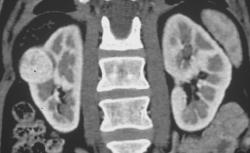

Retroaortic Left Renal Vein